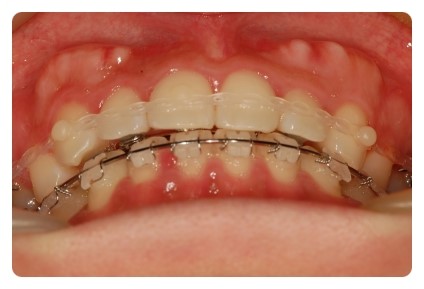

요쪽 송곳니도 조금 깨졌나 ;;

교정끝나면 치아미백이랑 충치치료랑 치아성형이랑 해야할듯요

확실히 고무줄까지 착용해서인지 틈이 금방금방 줄어드는것 같아요

하악도 이제 조금밖에 안남았어요

그런데 닫히고나면 어느정도까지 더 장치를 하고있어야될까요 ??

오래걸렸는데 ㅠㅠ 금방 돌아가버리진않겠죠 ;;